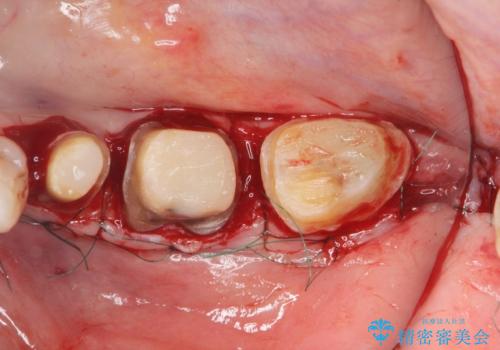

クラウンやレジン下に再発していた虫歯を丁寧に除去したのち、歯ぐきの腫れが改善が見られないため歯周外科を行い歯ぐきの状態を整えたのちにジルコニアクラウンを製作していきます。

クラウン治療を行う場合歯ぐきの腫れが、クラウン製作の精密さにおいて問題点となることがあります。

このような場合、歯周外科を行うことでクラウン周囲の歯茎の状態を整備し精度に優れる治療を行うことができます。